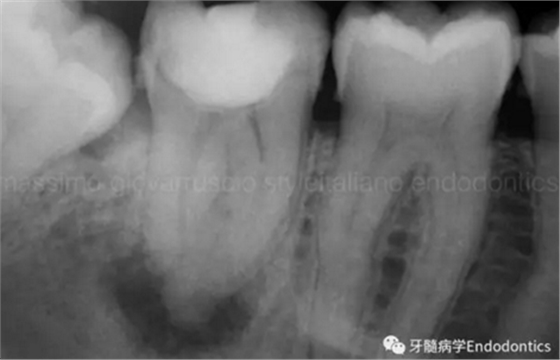

圖6.術(shù)后X線片顯示在根管機(jī)械預(yù)備后保留了原始的根管解剖形態(tài)結(jié)構(gòu)。冠方預(yù)敞和探查保證了對整個根管解剖形態(tài)結(jié)構(gòu)的保護(hù)。

圖7.具有解剖障礙的根管,比如根尖區(qū)不規(guī)則的直根管、存在不規(guī)則急彎的彎曲根管。